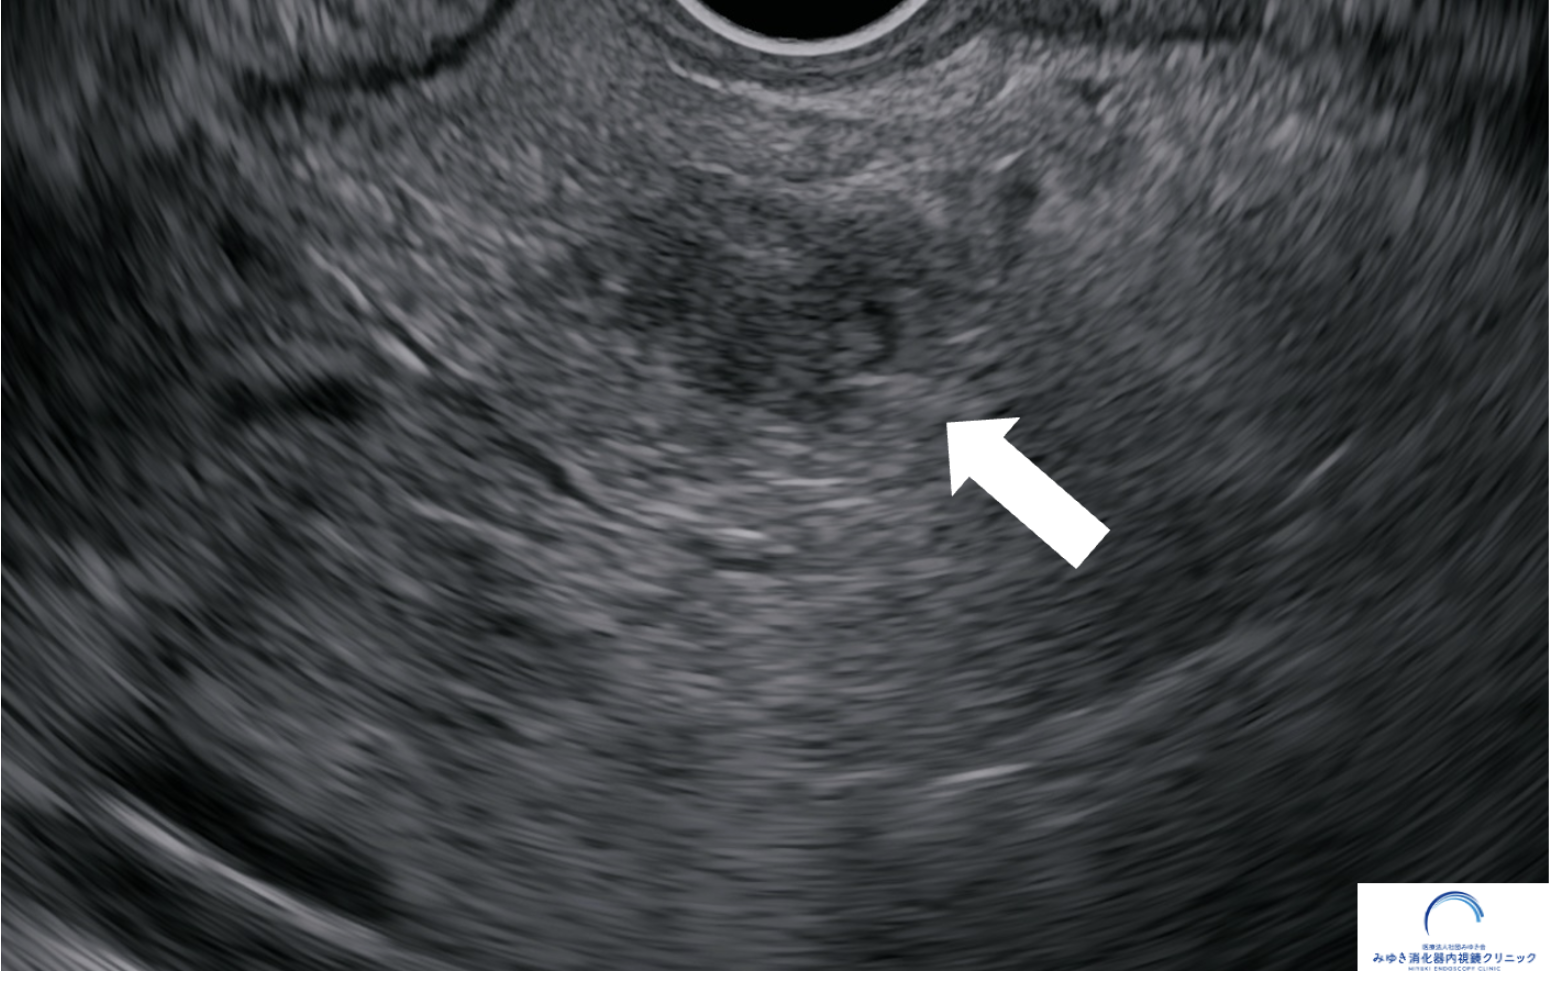

<膵しょう液性嚢胞腫瘍(SCN)>

CTやMRIの画像と比べて、超音波内視鏡検査では腫瘍内部の構造が詳細に観察できます